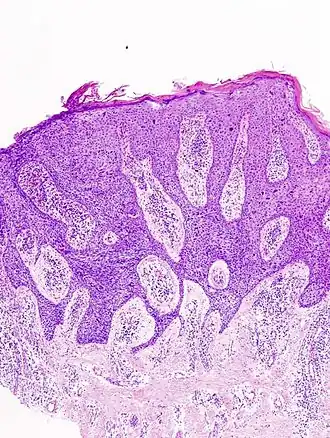

De diagnose morbus Bowen wordt gesteld door middel van histologisch onderzoek. De cellen van de opperhuid zien er dan onrustig (atypisch) uit: onregelmatig van vorm, wisselend van kleur, ongeordend van ligging. Bij morbus Bowen is deze onrust aanwezig over de gehele dikte van de opperhuid. Per definitie blijven de afwijkingen tot de opperhuid beperkt, en groeien ze niet de dermis (lederhuid) in, want dan zou er sprake zijn van een plaveiselcelcarcinoom. Echter in de praktijk is dit verschil niet altijd even duidelijk vast te stellen; ook getrainde pathologen komen vrij vaak tot uiteenlopende conclusies.[3][4]